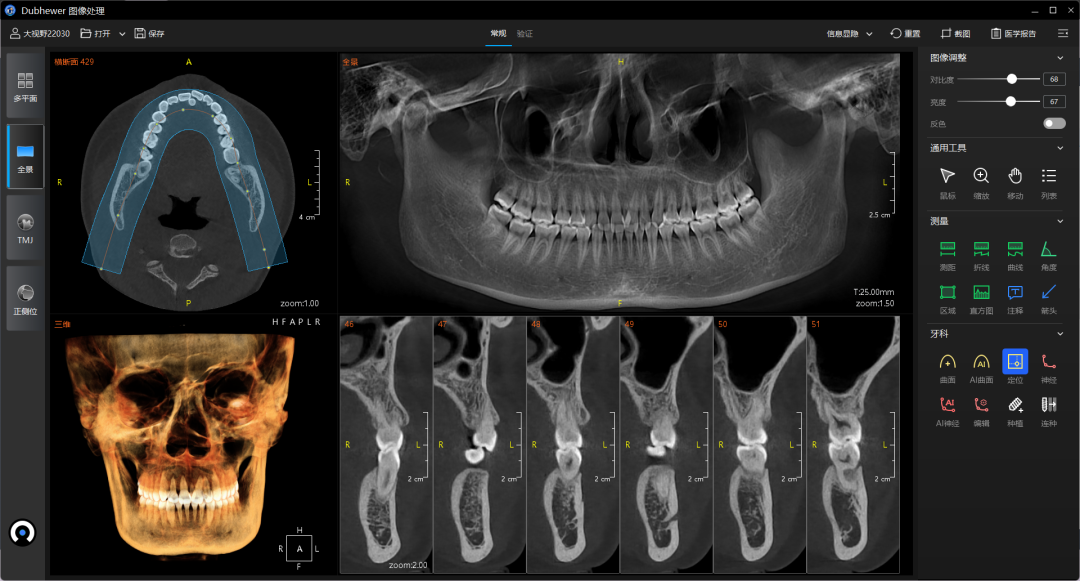

▲CBCT阅片软件

CBCT还有一大优势,就是通常会跟随设备一起推出配套的专业牙齿阅片软件。通过软件内置功能,可以自动生成没有重叠虚影的全景片,还可以通过图像分割获得单颗或多颗牙齿的“小牙片”。处理后的图像会自动修复畸变失真,图像更清晰、细节更完善,还能在三维平面内旋转观察,可以作为牙片机和全景机的优秀替代方案。